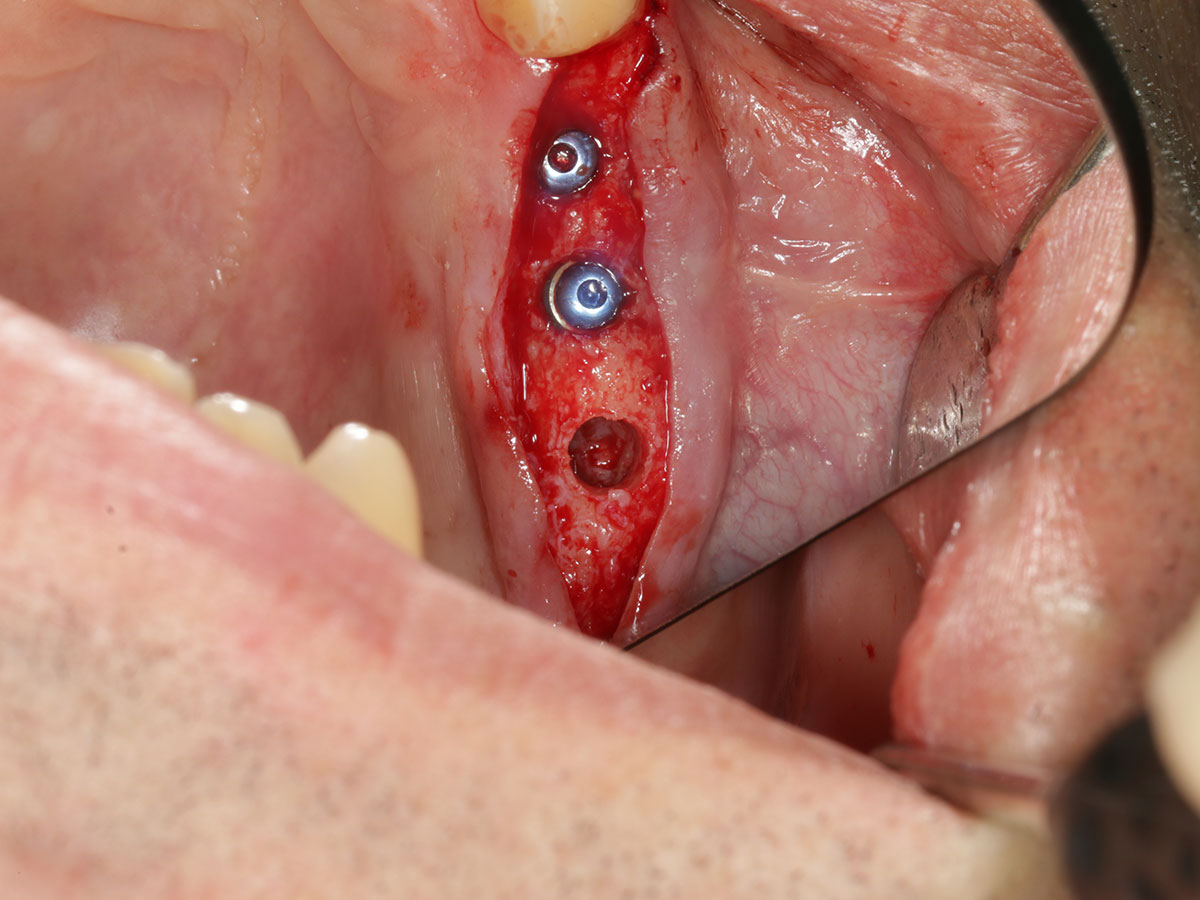

Umsetzung in die klinische Praxis

· Von der digitalen Planung zur chirurgischen Umsetzung

· Herstellung und Anwendung von Bohrschablonen

· Statische Navigation: Schritt-für-Schritt-Workflow und klinische Tipps